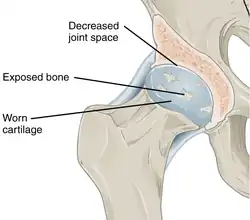

Annotated illustration of hip joint with osteoarthritis

Hip joint with osteoarthritis[36]

While osteoarthritis is a degenerative joint disease that may cause gross cartilage loss and morphological damage to other joint tissues, more subtle biochemical changes occur in the earliest stages of osteoarthritis progression. The water content of healthy cartilage is finely balanced by compressive force driving water out and hydrostatic and osmotic pressure drawing water in.[37][38] Collagen fibres exert the compressive force, whereas the Gibbs–Donnan effect and cartilage proteoglycans create osmotic pressure which tends to draw water in.[38]

However, during the onset of osteoarthritis, the collagen matrix becomes more disorganized, and there is a decrease in proteoglycan content within cartilage. The breakdown of collagen fibers results in a net increase in water content.[39][40][41][42][43] This increase occurs because whilst there is an overall loss of proteoglycans (and thus a decreased osmotic pull),[40][44] it is outweighed by a loss of collagen.[38][44]

Other structures within the joint can also be affected.[45] The ligaments within the joint become thickened and fibrotic, and the menisci can become damaged and wear away.[46] Menisci can be completely absent by the time a person undergoes a joint replacement. New bone outgrowths, called "spurs" or osteophytes, can form on the margins of the joints, possibly in an attempt to improve the congruence of the articular cartilage surfaces in the absence of the menisci. The subchondral bone volume increases and becomes less mineralized (hypo mineralization).[47] All these changes can cause problems functioning. The pain in an osteoarthritic joint has been related to thickened synovium[48] and to subchondral bone lesions.[49]